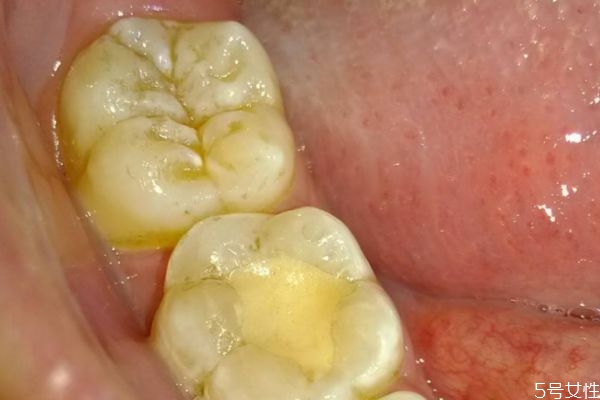

牙齦腫痛的絕大部分原因,還是牙結(jié)石或者說是軟垢的刺激。牙齒表面不干凈,軟垢以及結(jié)石的堆積,就會刺激這個牙齦,刺激牙齦的血管擴張,然后牙齦就會紅腫出現(xiàn)疼痛,經(jīng)常發(fā)生牙齦腫痛,必須要到醫(yī)院來進(jìn)行檢查。針對具體的情況,進(jìn)行具體的處理。如果是軟垢或者結(jié)石的刺激影響,那么主要的治療方法,還是進(jìn)行洗牙潔牙,或者說是超聲波潔治,如果長期出現(xiàn)牙齦腫痛,不處理的話病人一般會自己,第一次自己很難受,然后第二呢牙齦出血,也會對你的社交造成一些困擾。第三長期的牙齦腫痛,牙齒的炎癥得不到有效的控制,會使牙槽骨以及牙齦萎縮,那么牙齒會松動,牙齒松動以后,一般來說絕大部分情況,沒有辦法再恢復(fù)正常,會造成牙齒脫落。

牙齦腫的危害性是特別嚴(yán)重的,對于患者的牙齦健康損害嚴(yán)重,病發(fā)期間給患者帶來了困擾,甚至?xí)蓴_到工作以及生活,提醒各位朋友需要將牙齦腫了解透徹,平時的生活中多了解相關(guān)的誘發(fā)起因,生活中誘發(fā)牙齦腫的起因特別的復(fù)雜,主要包括牙周膿腫、牙齦膿腫、智齒冠周炎、根尖周炎等,這是都是常見的病因,很多人會因為這些病癥而出現(xiàn)牙齦腫痛的癥狀,從而侵害了牙齒及牙齦部位的健康。如果患者自身存在牙齦或者是牙周組織方面的慢性炎癥,特別是患者的機體抵抗力嚴(yán)重下降、天氣干燥、進(jìn)食辛辣及刺激性嚴(yán)重的食物時,都會導(dǎo)致原有的慢性炎癥產(chǎn)生急性的發(fā)作,繼而誘發(fā)了牙齦腫痛的癥狀,傷害了患者的牙齦健康,為此朋友們要注意口腔的衛(wèi)生,正確的刷牙,還要注意提早做一些牙齦腫痛的預(yù)防工作,這樣才能減輕牙齦腫的病發(fā)率,從而保護(hù)了人們的牙齦健康,遠(yuǎn)離了疾病的困擾和損害。